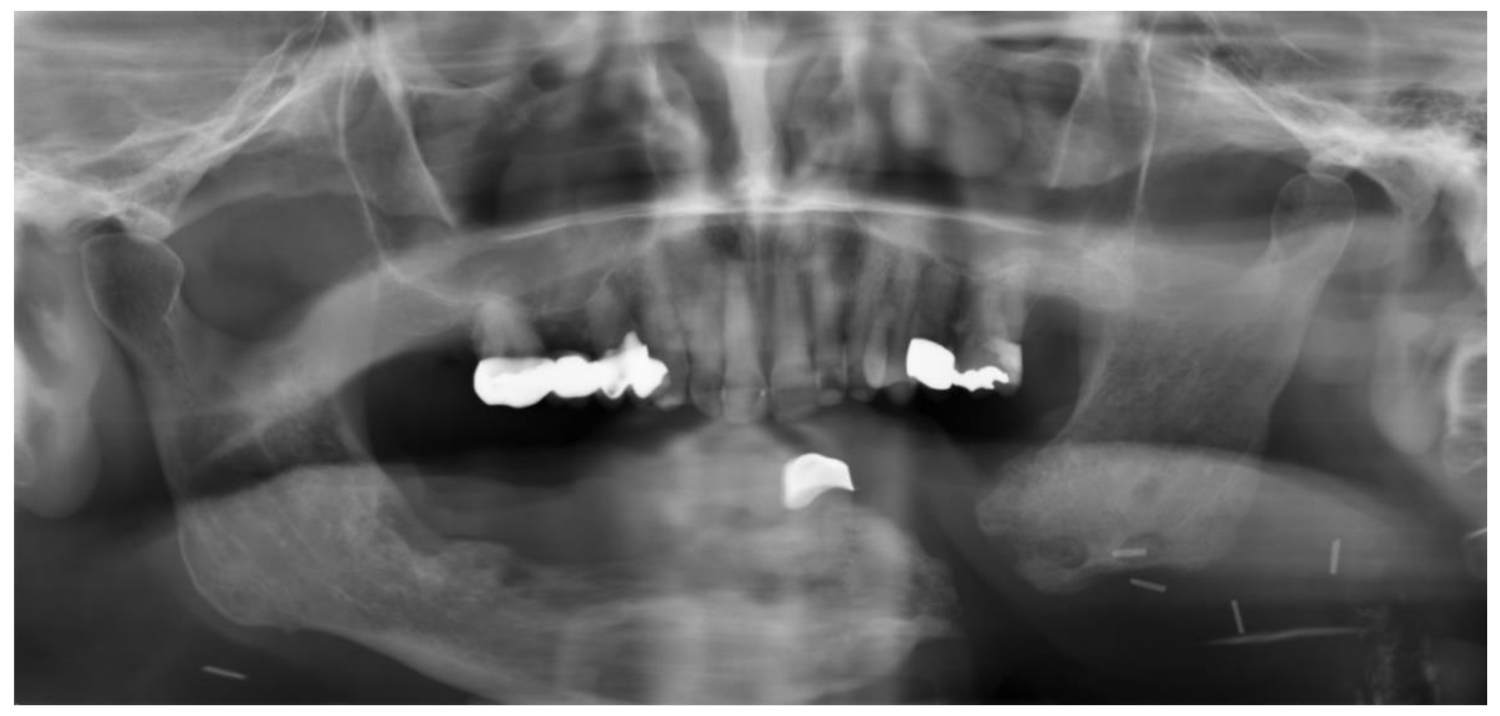

Partial mandibular resection with complete transection of the mandibular bone without reconstruction will lead to mandibular dislocation and functional asymmetry (Figure 8 and Figure 9). Radiation and scarring may even increase structural and functional asymmetry. Therefore, surgical reconstruction of the mandible is the therapy of choice whenever it is possible [123].

Figure 9.

Panoramic radiograph of the same patient three years later after further tooth loss.